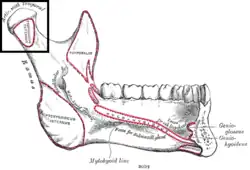

Mandible. Outer surface. Side view. (Condyle and neck labeled at upper right.)

Inner surface of mandible. Condyloid process is at upper left.

Inner surface of mandible. Condyloid process is at upper left. -